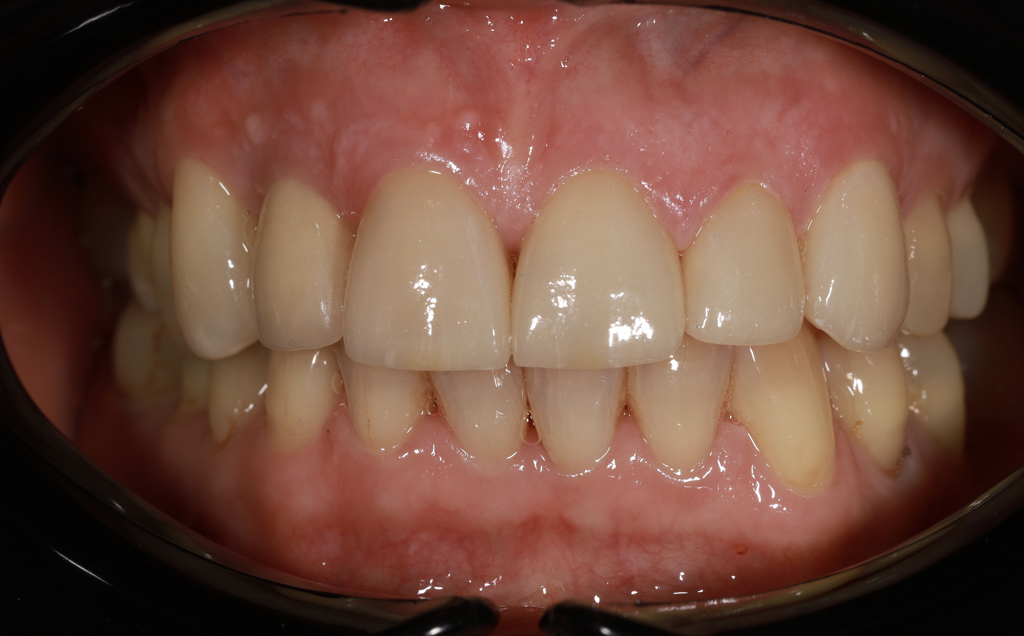

Zaprezentujemy serię poruszających historii pacjentów, którzy zdecydowali się na kompleksowe leczenie dentystyczne. Od przypadków zaawansowanej próchnicy, przez wypadki, które wymagały rekonstrukcji zębów, po pacjentów marzących o hollywoodzkim uśmiechu dzięki zastosowaniu licówek – każda historia jest dowodem na to, jak nowoczesna stomatologia może odmienić życie.